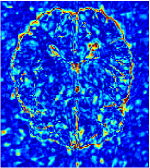

Qualitative comparison between conventional and Meta-learning methods are shown in Figure 1 and 3, which display the reconstructed MR images of the same slice for T1 and T2 respectively, we label the zoomed-in details of HGG in the red boxes. We observe the evidence that conventional learning is more blurry and lost sharp edges, especially in lower CS ratios. From the point-wise error map, we find meta-learning has the ability to reduce noises especially in some detailed and complicated regions comparing to conventional learning.

In general supervised learning, training data need to be in the same or similar distribution, heterogeneous data exhibits different structure variations of features which hinders CNNs to extract features efficiently. In our experiments, raw measurements sampled from different ratios of compressed sensing display different levels of incompleteness, these undersampled measurements do not fall in the same distribution but they are related. Different sampling masks are shown at the bottom of Figure 1 and 2 may have complemented sampled points, in the sense that some of the points which sampling ratio mask does not sample have been captured by other masks. In our experiment, different sampling masks provide their own information from their sampled points so that four reconstruction tasks help each other to achieve an efficient performance. Therefore, it explains the reason that Meta-learning is still superior to conventional learning when the sampling ratio is large.